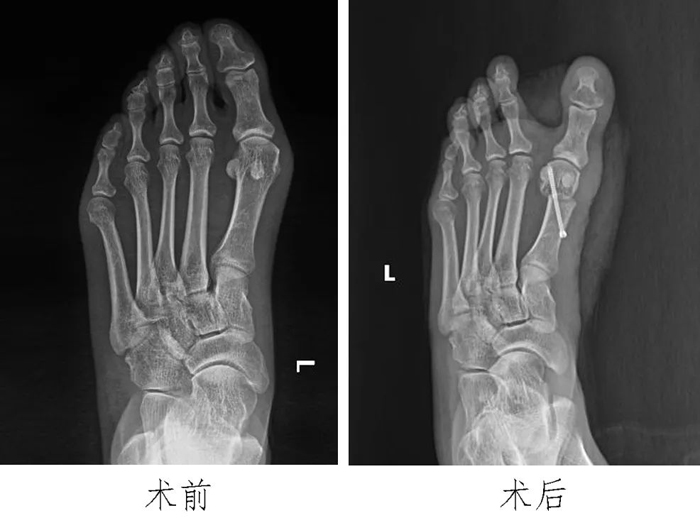

1?踇外翻:

傳統(tǒng)的踇外翻多為兩處大切口,我們采用微創(chuàng)單一內(nèi)側(cè)小切口治療踇外翻,術(shù)后踇外翻矯正良好,患者滿意度高。